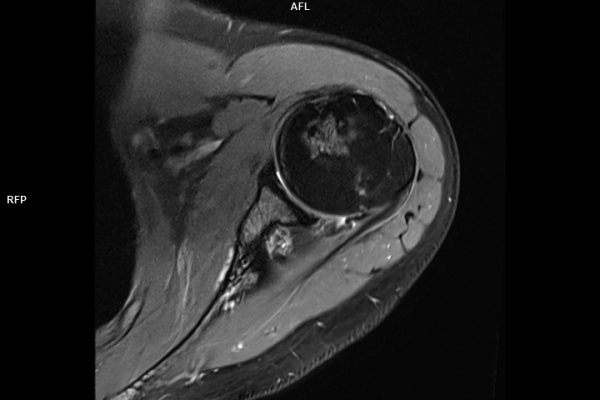

Detailbild MRT

Wir verbinden modernste Medizin mit einer Atmosphäre, in der Sie sich sicher und gut aufgehoben fühlen. Klare Abläufe, Ruhe und Zeit für Sie stehen im Mittelpunkt jeder Untersuchung. CT- und MRT-Bilder ohne Wartezeit. Mit Photon-Counting-CT und 3-Tesla-MRT setzen wir auf in Kärnten einzigartige Technologien für außergewöhnlich detailreiche Bilder und besonders präzise Diagnosen. Die schonenden Verfahren eignen sich auch für Kinder und Jugendliche. Kurze Messzeiten, große offene Geräte und ein ruhiges Umfeld sorgen für eine angenehme Untersuchung und ein gutes Gefühl von Anfang bis Ende.

Die MRT (Magnetresonanztomographie) arbeitet mit Magnetfeldern und Radiowellen und eignet sich besonders für Untersuchungen der Weichteile wie Gehirn, Muskeln oder Gelenke. Die CT (Computertomographie) nutzt Röntgenstrahlen und liefert schnelle, hochauflösende Bilder, insbesondere für Knochen, Lunge oder innere Organe. Die Wahl der jeweiligen Untersuchung richtet sich an das individuelle Krankheitsbild und wird bei der Überweisung festgelegt.